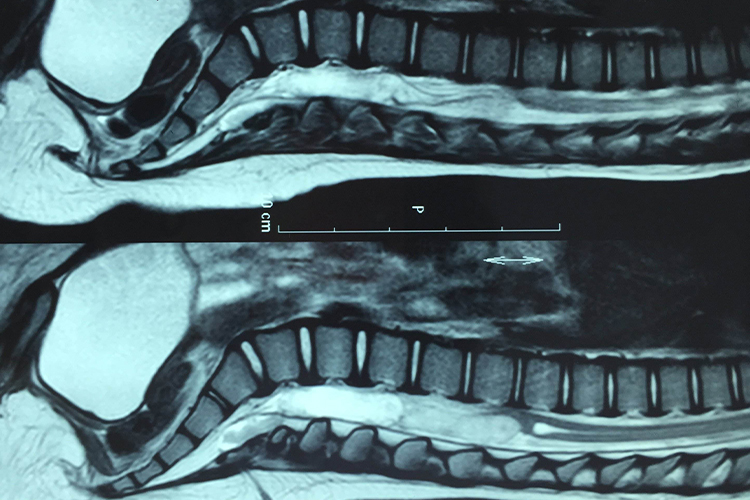

小儿先天性皮毛窦通常临床表现无症状,或仅有不易察觉的小孔,即窦口,偶尔可见患处皮肤凹陷;继发感染时窦口可有脓液流出,也可以在影像学下观察到由从皮肤延伸到椎管内的真皮窦。